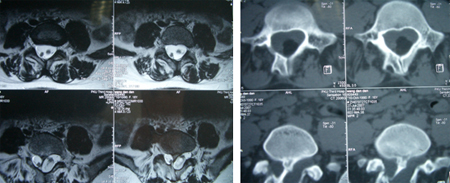

术中发现L4-5椎板异常增生肥厚,L5椎板伸入椎管内形成骨嵴,脊髓圆锥低位在L4水平,L4以下肿瘤组织为多种成份,近端为脂肪组织,S1水平分为两种肿瘤成份,内侧为清亮粘液状物、外侧为珍珠样角化物。

术后病理结果为成熟性囊性畸胎瘤。术后图片